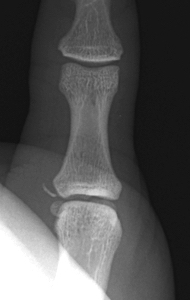

MRI

Anatomy

A. Undisplaced

![]()

Distal tear of ulna collateral ligament on coronal MRI